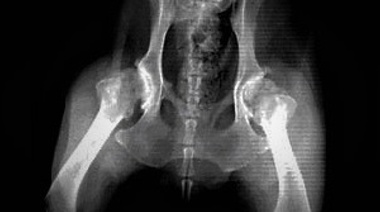

Tag: Osteoartritis canina

Osteoartritis canina: Nuevas pautas de consenso internacional

Análisis científico sobre los tratamientos para la osteoartritis canina